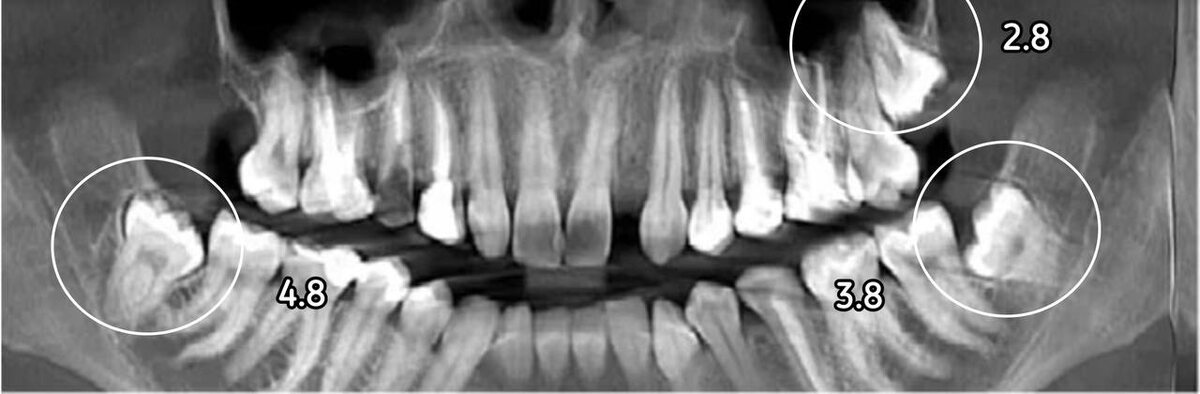

Под удаление у пациентки идут зубы 2.8, 3.8 и 4.8. Все эти «восьмерки» ретинированные и дистопированные👇

Зубы под удаление

Ситуация Анастасии достаточно сложная. Ее зубы располагаются очень глубоко внутри толщи кости.